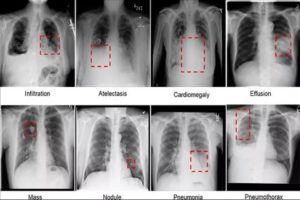

Теперь рассмотрим различные виды пневмонии на фото рентгеновских снимков.

Данному виду патологии свойственно поражение небольших участков легочной ткани.

Изображение очаговой пневмонии прослеживается плохо, затемнения могут быть средней или вовсе слабой интенсивности.

Размеры очагов поражения в среднем достигают полутора сантиметров, при отсутствии лечения их количество увеличивается. На фото ниже изображен пример правосторонней очаговой пневмонии.

Данной форме характерно формирование больших участков поражения легочной ткани. Патологический процесс может охватывать как одно, так и оба легких. На иллюстрации ниже показана тяжелая форма крупозной пневмонии.

При сегментарной форме происходит поражение целого сегмента легкого. При этом пораженный участок исключается из процессов газообмена, что приводит к серьезным затруднениям дыхательного процесса. На иллюстрации ниже изображена правосторонняя сегментарная пневмония.

Происходит поражение соединительной ткани, окружающей альвеолярные структуры и кровеносные сосуды легких. На снимке характеризуется формированием участка уплотнения малой интенсивности, может поражать обе доли дыхательного органа. На фото ниже множество светлых разводов в легочном рисунке говорят о наличии интерстициальной инфильтрации.

При рентгенографическом исследовании каждый вид пневмонии выглядит по разному и таким образом заболевание можно диагностировать. Рассмотрим различные виды пневмоний, их изображения на снимках и пояснения.

Очаговая (или очагово-сливная) форма пневмонии – очаги инфильтрации имеют диаметр 0,5-1 см и локализуются в одном или нескольких сегментах легкого. Иногда поражения могут располагаться билатерально.

При абсцедирующей пневмонии на снимке отчетливо видно тотальное затемнение области инфильтрации и уплотнение плевры; наблюдаются полости до 2 см, в которых скапливается гнойная жидкость.

При аспирационной пневмонии на рентген-снимке видны закупорки бронхов в виде треугольных теней. Диафрагма при этом приподнята.